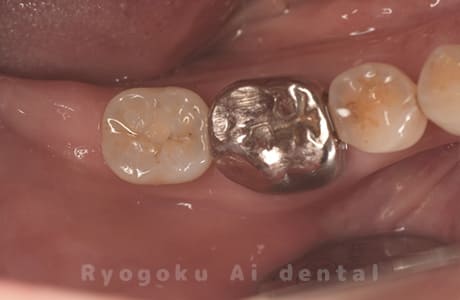

Case08

-

- 原因

- 左下7番歯根破折

- 治療内容

- インプラント治療

- 治療費用

- 約600,000円

左下の腫れが治らないとの事でご来院された患者様です。歯が割れていたため、抜歯を行い、骨に代わるお薬を入れ、インプラントを埋入致しました。経過良好で大変満足していただけました。

<リスク・副作用>

治療後、痛みや違和感、出血、腫れなどが出る事があります。喫煙者、糖尿病などの方の場合、歯が生着しない場合があります。